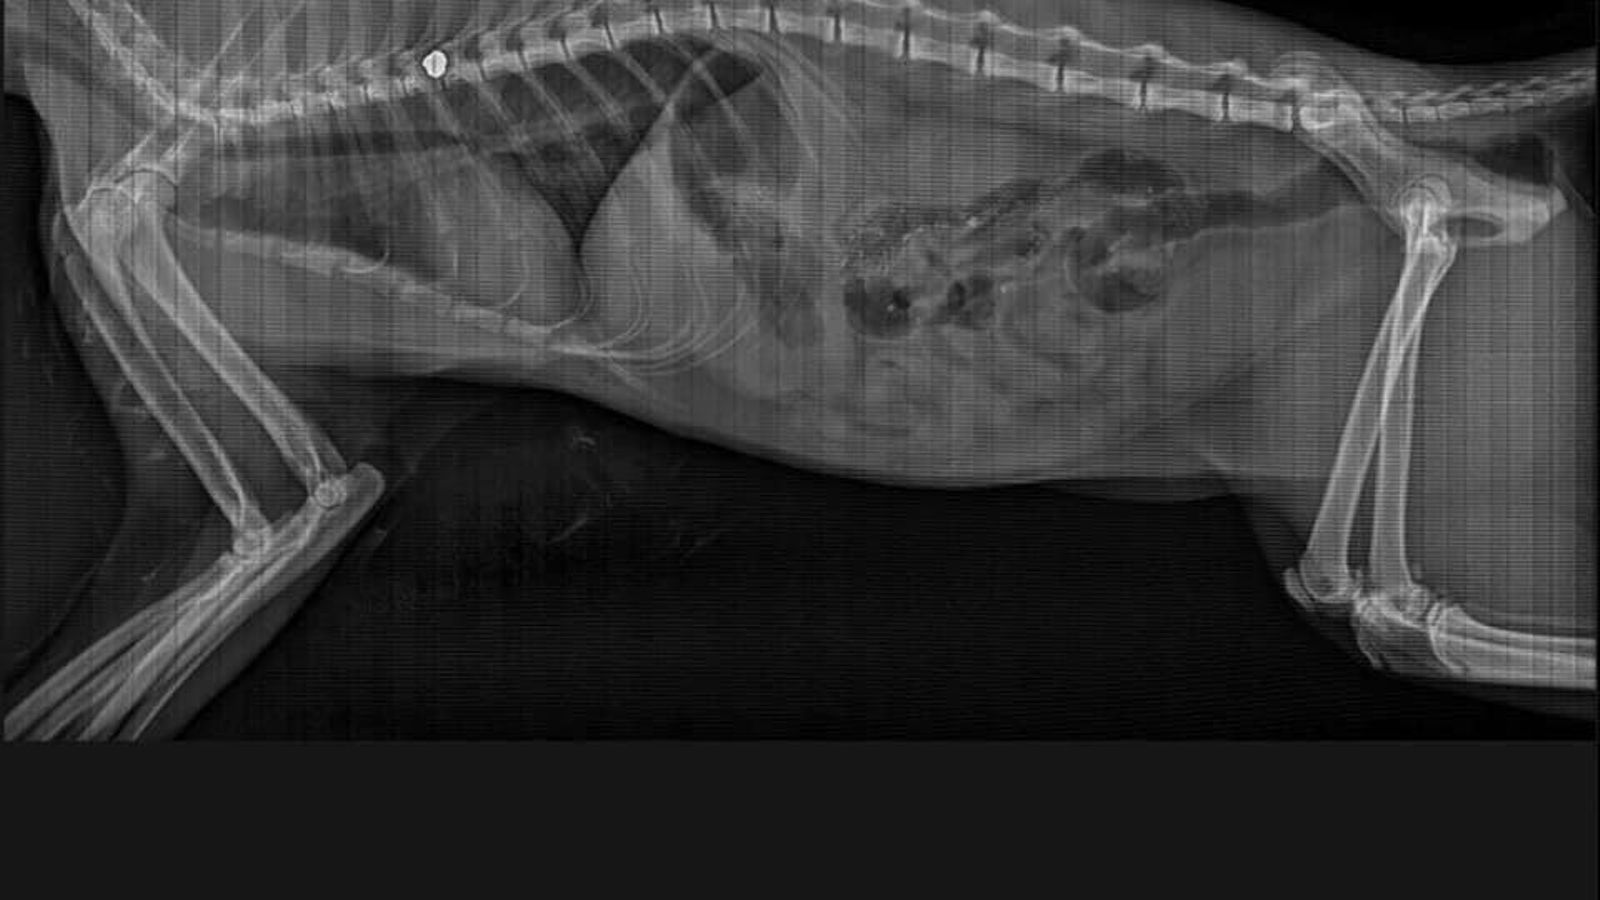

Radiografía del gato herido por un disparo.

Radiografía del gato herido por un disparo. / M. H.

Guerrero detalla que el balín se encuentra en la columna vertebral y, al parecer, la propia inflamación es la que le impide mover las patas. Además, el presidente de la organización apunta que al tratarse de un gato callejero "es más complicado porque su cuerpo tiene menos fuerza".